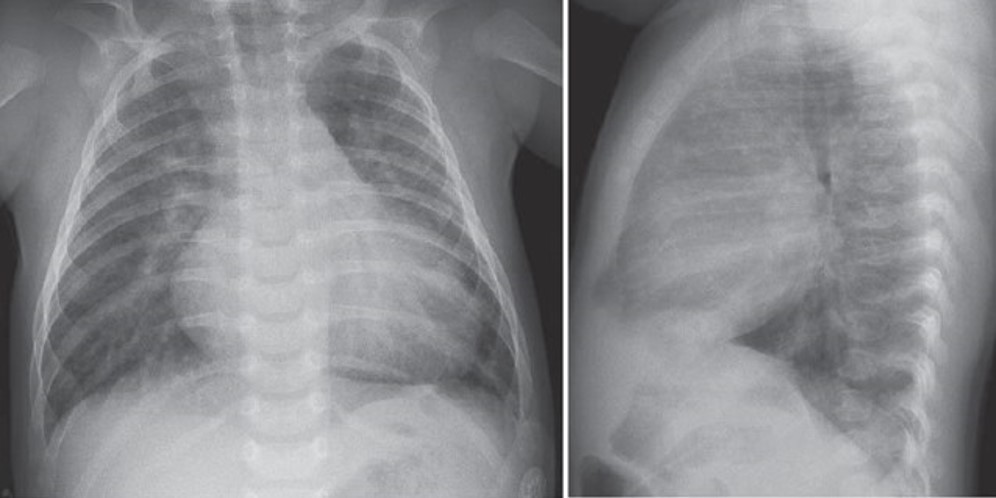

Photo: Wells RG. Diagnostic Imaging of Infants and Children; 2015.